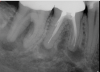

(5.) Preoperative radiograph of tooth No. 19 following a pulpectomy procedure that was complicated by an intraoperative furcal perforation.

Figure 5

(6.) Postoperative radiograph showing immediate perforation repair using MTA followed by complete obturation.

Figure 6

(7.) One-year follow-up periapical and bitewing radiographs demonstrating the absence of apical pathosis or furcal pathosis at the site of

the perforation.

Figure 7

(8.) One-year follow-up periapical and bitewing radiographs demonstrating the absence of apical pathosis or furcal pathosis at the site of

Figure 8